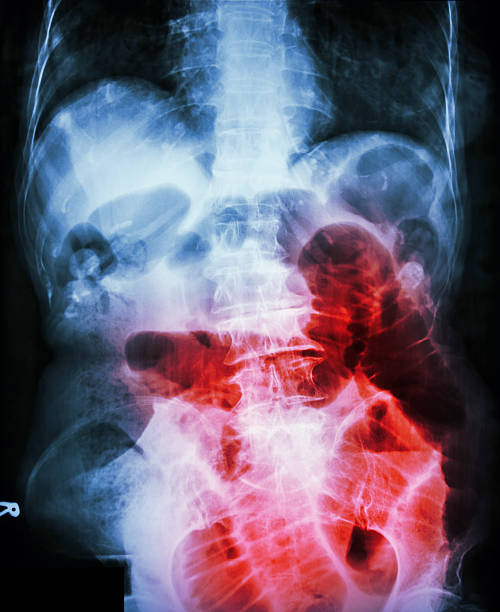

배탈, 복부 부기, 가스 증상

장폐색으로 인한 배탈, 복부 부기, 가스 증상은 대장 내부에서 음식물이 충분히 소화되지 않아 대장 내부의 미생물들이 과다하게 생성되거나 대장 내부에서 가스가 축적될 때 나타날 수 있습니다. 이러한 증상은 대장 내부에서 음식물이 충분히 소화되지 않아 대장 내부의 환경이 변화됨에 따라 생기는 증상으로, 복부 팽만감, 가스 착증, 배뇨 등이 나타날 수 있습니다.